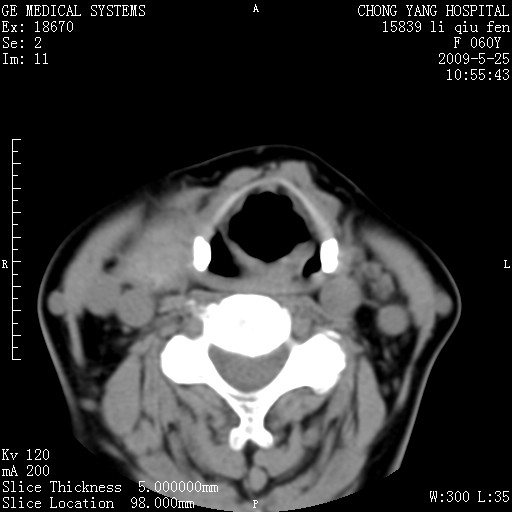

女。65岁头疼,多发硬化病史5年,近十余天加重

北京天坛,结论:多发硬化